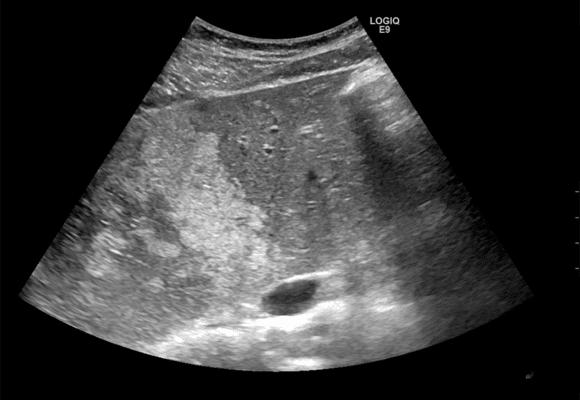

Το λιπώδες ήπαρ (ήπαρ με λιπώδη διήθηση) είναι μια πάθηση κατά την οποία συσσωρεύεται υπερβολικό λίπος στα ηπατικά κύτταρα.